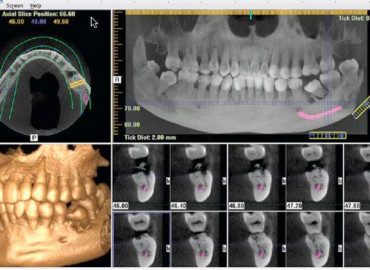

Dental x-rays help your dentist see underlying issue not obvious to the naked eye. The arrows show dental decay and the areas most commonly affected by dental decay. Do you really need dental X-rays? Yes, absolutely. Dental X-rays are a screening procedure that allows the dentist to get “the full picture” and to understand what […]